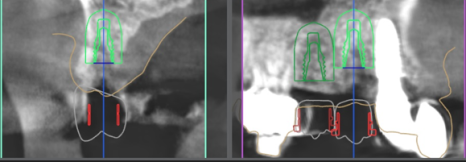

디지털 임플란트 진단을 하면서,

apical lesion(뿌리 염증) 이 있는것이 관찰이 되며

당일 발치 후 즉시식립을 하기로 했습니다.

근데.. 이미 치조골이 많이 얇죠?

전치부쪽이기 때문에

어금니 뼈 보다 더 얇습니다.ㅠㅠ

이렇게, 얇은 뼈에 임플란트를 심으려니,

정확한 진단을 해야 됩니다.

그래서, 위에서 볼 수 있는 사진들 처럼

여러가지 방법을 동원하여 현 상황을

정확히 분석을 해야 되겠죠.